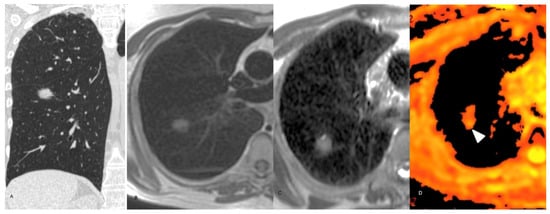

3. Results

3.2. MR Findings

4. Discussion